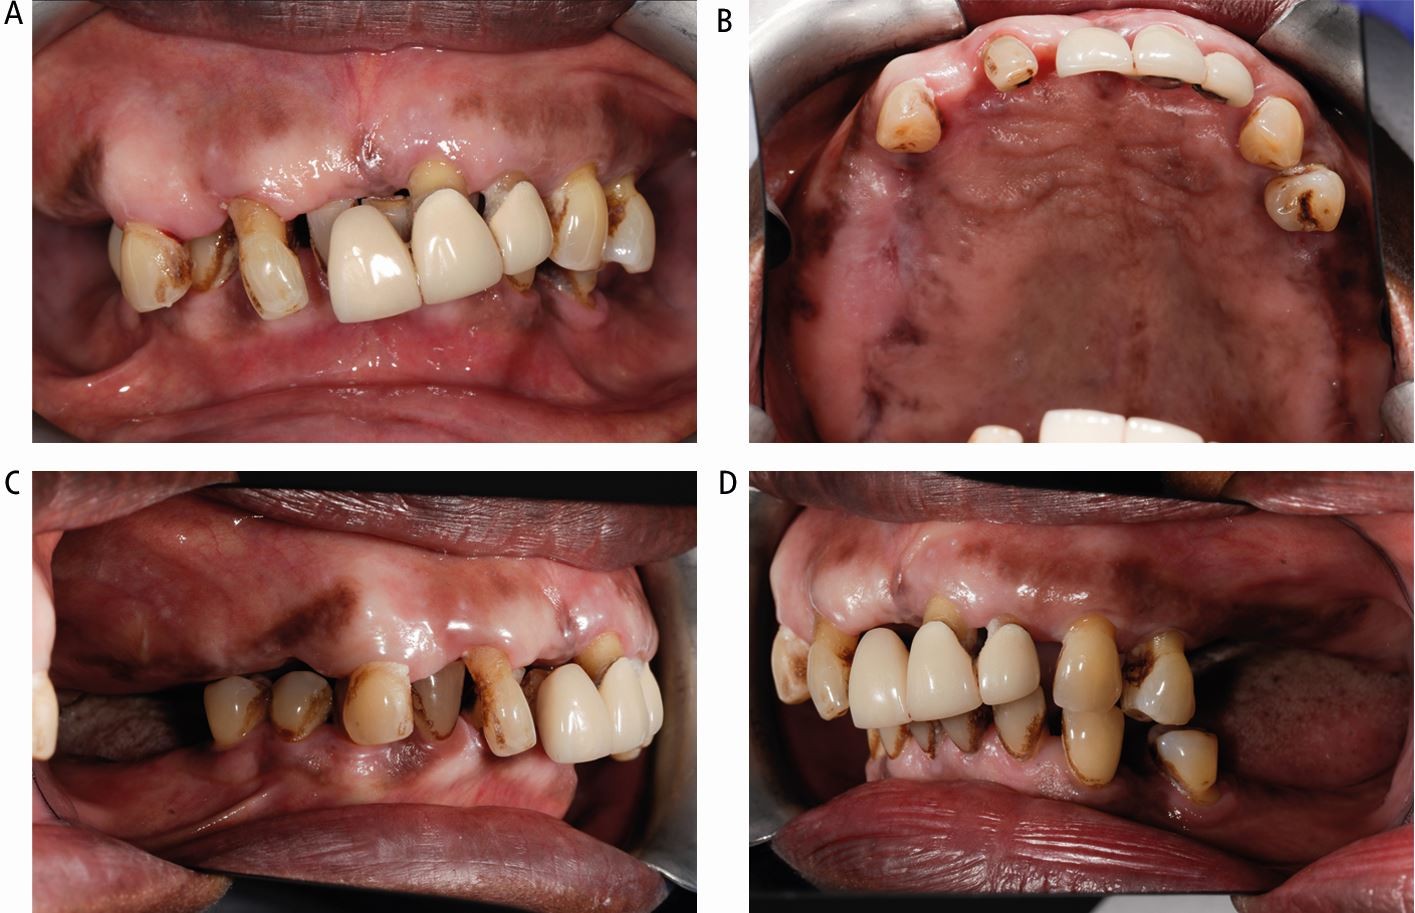

Fig. 10

Case 2: intra-oral views. (A) Right cant with teeth in occlusion. (B) Palatal view showing the bony expansion of the right maxilla. (C, D) Right and left lateral views showing the lack of interocclusal space on the right side